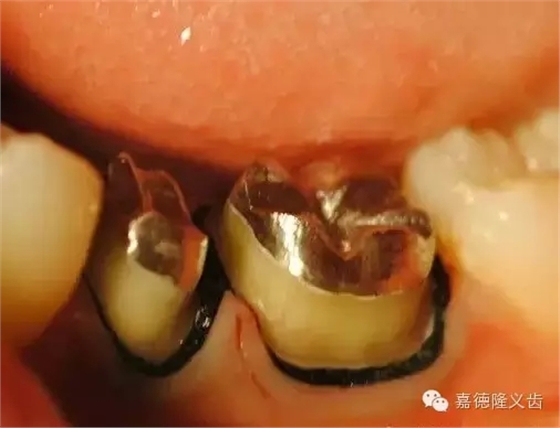

通常技师制作成平面桩核,造成颌面修复难度。如图:

比较图

牙体预备图(1)

牙体预备图(2)

牙体预备图(3)